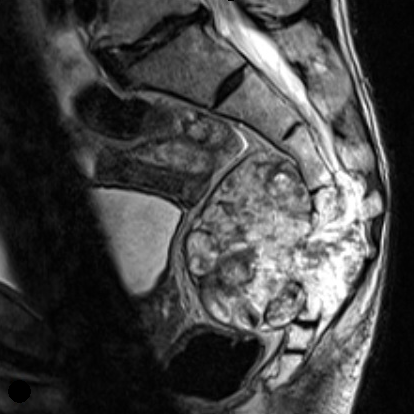

The workup for a suspected chordoma consists of appropriate imaging followed by a biopsy of the tumor to confirm the diagnosis. Chordomas may be difficult to appreciate on plain x-rays, and both computed tomography (CT) and magnetic resonance imaging (MRI) scans are needed to adequately visualize the tumor. Figure 1.

Figure 1: CT and MRI of a Sacral Chordoma (within red circle).